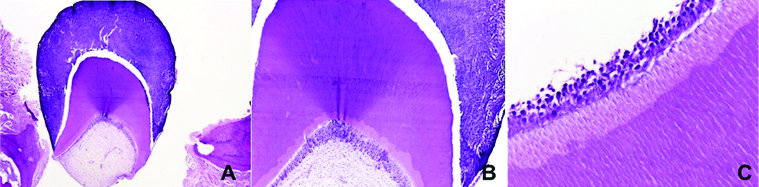

The macroscopical exam revealed 12 pieces of tooth-like structures with hard consistency and different sizes, measuring 15×11×7 mm in total. In addition, another part of the lesion was formed by soft tissue with fibroelastic consistency and brownish colour, measuring 10×7×6 mm. Microscopically, the lesion presented a constitution similar to normal dental tissues, with enamel, dentin, and dental pulp cells [Table/Fig-4]. The analysis confirmed the diagnosis of compound odontoma.

a,b) Histopathological aspects of compound odontoma, showing a malformed tooth germ composed of enamel, dentin, and pulp. c) Presence of odontoblasts forming dentin (stained with H&E; a: 40X, b: 100X, c: 400X).